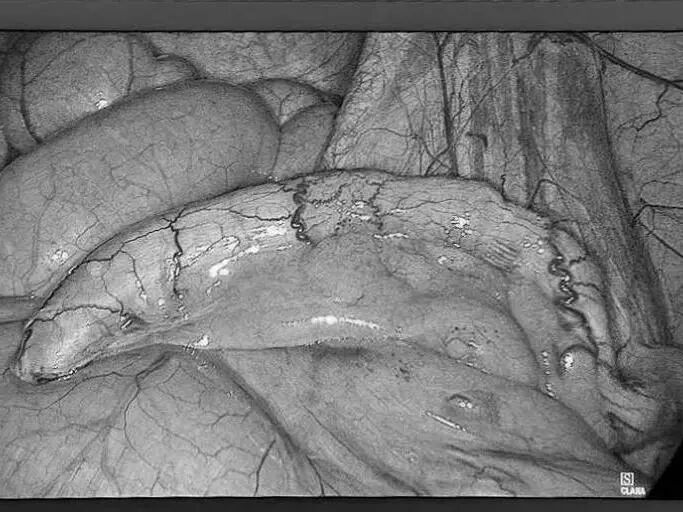

为深入践行人才强院核心战略,加速打造高水平医疗专家团队,引领学科跨越式发展,7月15日,贵州航天医院成功签约(柔性引进)知名肛肠外科专家高大勇教授,并举行“高大勇教授名医工作室”授牌仪式。贵州航天医院党委书记杨军,院长廖江荣,副院长彭亮、马庆庆、蒋婷出席仪式,普外科全体医护人员参加。 仪式上,杨军为高教授颁发了聘书,双方共同签署了合作协议,高教授授予普外科“名医工作室”函牌。 聘书颁发 柔性人才引进协议签约 名医工作室授牌 仪式后,高大勇教授前往科室开展早交班、教学查房等工作,针对疑难病例给予专业的治疗建议和科学指导。 此次柔性引进高大勇教授并设立名医工作室,将进一步促进贵州航天医院普外科在学科建设、技术创新、人才培养、科研教学等方面能力的提升,推动我院肛肠疾病诊疗能力实现跨越式发展,为广大患者带来优质医疗服务。 贵州航天医院普外科专家团队 高大勇 普外科(肛肠外科)学科带头人、名誉主任,主任医师、教授 临床擅长:对中西医结合诊治肛肠学科各种常见病、多发病及疑难杂症等具有丰富的临床经验。 原遵义市第一人民医院(遵义医科大学第三附属医院)、遵义市中医院肛肠科主任。中华中医药学会肛肠分会常委,全国中医肛肠学科名专家,中国健康促进与教育协会肛肠分会常委,中国康复医学会肛肠疾病康复专业委员会常委,中国民间中医医药研究开发协会肛肠分会副秘书长,中国医师协会中西医结合肛肠医师专业委员会常委,国家二级心理咨询师,贵州省第一批中医名医工作指导老师,遵义市名中医,遵义市肛肠学会会长,遵义市肛肠质控中心名誉主任,遵义市中西医结合学会名誉会长,遵义市健康科普专家,原贵州省中西医结合学会肛肠分会副主任委员、贵州省中医肛肠质控中心副主任、遵义市医学会医疗鉴定委员会专家、遵义市卫生系列高评委。发表论文30余篇,主编和参编医学著作5本,主持省级科研课题2项、市级科研课题2项、院级科研课题1项。 梁 跃 中共党员,普外科党支部书记、主任,主任医师 临床擅长:对普外科各类肿瘤手术具有丰富的临床经验。 毕业于遵义医学院,遵义市医学会小儿外科学分会常务委员,遵义市肛肠协会理事,遵义市医学会核医学分会(第二届)委员会委员;荣获第三期“黔医人才计划”优秀学员称号;主持市级课题1项,完成省级课题1项,在国内各类刊物上发表论文10余篇。 钱科洪 民盟盟员,普外科副主任医师 临床擅长:从事普外科临床工作30余年,对各类普外科疾病的诊治,乳腺、甲状腺、胃十二指肠、结直肠等疾病及疑难杂症诊治具有丰富的临床经验。 毕业于遵义医学院临床医疗系,2009年前往中山大学附属第一医院微创外科进修学习,在国内各专业期刊发表论文数篇。 贵州航天医院普外科简介 基本情况 贵州航天医院普外科成立于1968年,前身属于航天部O61基地3417医院外一科,1998年3417医院、3427医院合并后更名为普外科,下设胃肠外科、肛肠外科2个亚专业科室,拥有在全市较为先进的专科设备和技术,是中国疝病专科联盟单位,贵州医科大学附属医院胃肠外科专科联盟单位。开放床位40张,配备医护人员21人。 专科特色 普外科致力于胃肠及肛肠疾病的外科临床诊治及科研,以腹腔镜微创外科技术为本,形成以快速康复治疗胃肿瘤、结直肠肿瘤、小肠肿瘤、直肠脱垂、肥胖病、急腹症、各类疝、痔、瘘等专科特色,同时注重胃肠疾病尤其是结直肠恶性肿瘤的基础研究和临床转化研究,总体诊断和治疗水平在区域同级医院居于领先水平。 开展手术:腹腔镜下胃癌根治术,腹腔镜下袖状胃切除术,腹腔镜下胃肠道间质瘤切除术,腹腔镜下结、直肠癌根治术,胃癌、结直肠癌的精准治疗,腹腔镜下小儿疝气、成人疝修补术,腹腔镜下阑尾手术,内痔的硬化注射治疗及痔疮的微创治疗:ATH、PPH、TST,直肠脱垂的各种手术治疗,难治性伤口VSD技术,鼻胃肠管、肠梗阻导管置入术,肛肠术后间歇性导尿技术,并引进了中医适宜技术,也为各种化疗患者提供输液港安装,提高患者就医体验。 腹腔镜下腹股沟 疝无张力 修补术 腹股沟疝里金 斯坦(Lichten stein)手术 PPH微创术治疗环状混合痔 黏连性或炎性肠梗阻-肠梗阻导管 腹腔镜袖状胃切除 腹腔镜阑尾切除术 腹腔镜阑尾肿瘤切除术 腹腔镜下结肠癌根治术 诊疗范围 胃肿瘤、结直肠肿瘤、小肠肿瘤、肥胖症、各类急腹症、腹部外伤、腹壁疝、便秘、直肠脱垂、痔疮、肛瘘、肛裂等胃肠、肛肠外科疾病。 END